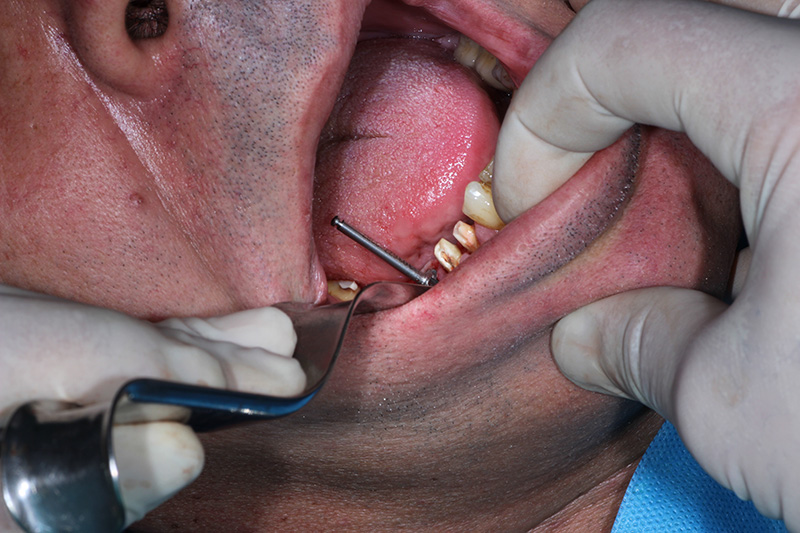

26-ого октября в учебном центре Стом-Лайн был проведен мастер-класс на тему «Закрытый и открытый синус-лифтинг при имплантации, с использованием имплантатов Thommen Medical». Мастер-класс провел главный врач-стоматолог клиники «Нюанс» в Москве Мхитар Казарян.

Мастер-класс начался с представления швейцарских имплантатов Thommen Medical, официальным предтсвителем которых является клиника Стом-Лайн. Далее были проведены обсуждения предстоящей операции и исследования компьютерной томографии, после чего участники смогли присутствовать на операции или следить за ней из учебного центра.

Во время операции доктор Казарян представил на практике особенности и преимущества имплантатов Thommen Medical.